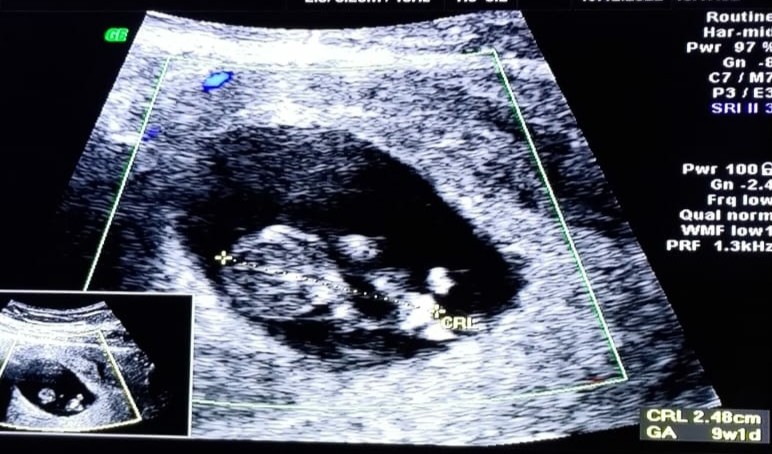

Ale były emocje! Serduszko bije 173 bpm❤ na chwilkę lekarz nam włączył dźwięk. Miało być 9t+0, ale wyszło 9t+1. "Calineczka" jak nazwał lekarz dziecko ma już 2,48 cm

Ale były emocje! Serduszko bije 173 bpm❤ na chwilkę lekarz nam włączył dźwięk. Miało być 9t+0, ale wyszło 9t+1. "Calineczka" jak nazwał lekarz dziecko ma już 2,48 cmdzisiaj chyba nie będę miała drzemki w trakcie dnia, za dużo emocji